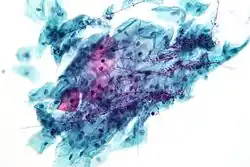

![]() High-grade squamous intraepithelial lesion | |

- High-grade squamous intraepithelial lesion (HGSIL or HSIL)

In a typical scenario, about 0.5% of Pap results are high-grade SIL (HSIL), and less than 0.5% of results indicate cancer; 0.2 to 0.8% of results indicate Atypical Glandular Cells of Undetermined Significance (AGC-NOS).